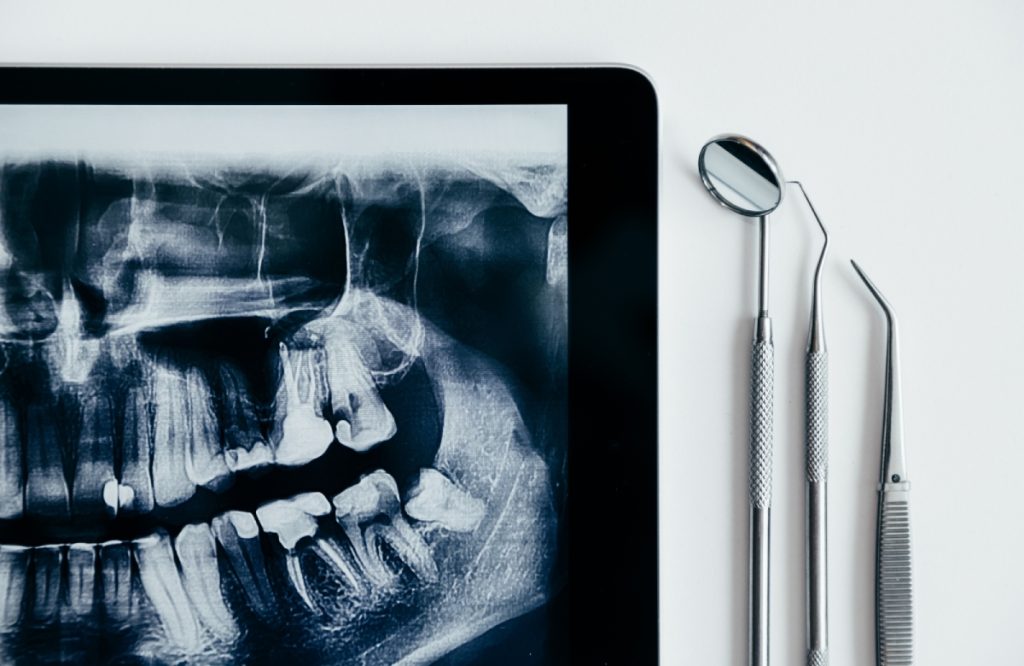

Chụp X-quang răng là một phương pháp hình ảnh y học sử dụng tia X để tạo ra hình ảnh của các cấu trúc và mô trong vùng răng và xương hàm của bệnh nhân. Quá trình này giúp bác sỹ nha khoa đánh giá và chẩn đoán các vấn đề về răng và xương hàm một cách chi tiết hơn so với kiểm tra bề mặt của răng bằng mắt thường.

Trong trường hợp cần kiểm tra toàn bộ khoang miệng, các bác sỹ sẽ chỉ định chụp X quang toàn cảnh răng. Phương pháp này còn được gọi là chụp Panorama răng, giúp ghi lại hình ảnh sắc nét, độ phân giải cao.

Chụp X quang toàn cảnh răng áp dụng nguyên lý chụp cắt lớp vi tính cổ điển với chùm tia X đi qua một khe hẹp, cho phép nhìn được hình ảnh các thành phần trong bề mặt lớp cắt rồi sử dụng thuật toán máy tính để tạo ảnh một cách sắc nét nhất. Bệnh nhân sẽ được mặc áo chì bảo vệ, cắn vào một tấm nhựa cố định sẵn trên máy rồi đứng yên trong thời gian chụp. Máy chụp X quang răng sẽ bắt đầu làm việc, bóng X quang và tấm cảm biến (phim) sẽ di chuyển ngược chiều nhau, quay một vòng quanh xương hàm dưới của bệnh nhân trong khoảng thời gian từ 12 đến 15 giây.

Hình ảnh Panorama răng sẽ cho thấy chi tiết về xương hàm trên và xương hàm dưới, các thành phần lân cận, khớp thái dương hàm hai bên và xoang vùng mũi. Đặc biệt, phương pháp chụp X quang răng toàn cảnh giúp bác sỹ có thể quan sát được toàn bộ hai cung răng trên cùng một phim. Do đó, kỹ thuật này có thể giúp chẩn đoán nhiều loại bệnh lý răng miệng khác nhau như răng mọc lệch, răng mọc ngầm, u nang, áp xe, tổn thương ở xương hàm….